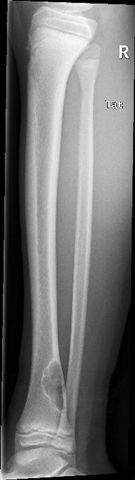

El Caso Clínico de los Jueves CAso n º 3. Una placa que asusta

Paciente de 15 años que consulta por dolor en tercio inferior de pierna dercha desde hace un mes sin antecdente traumático alguno. El dolor no le despierta de noche y aparece , de predominio tras la realización de ejercicio intenso, aunque no siempre. Remite con Ibuprofeno 600 mg cuando le duele. A la exploración no se aprecian alteraciones cutáneas, no hay signos inflamatorios y no presenta dolor a la presión manual en dicha zona. No fiebre ni signos de enfermedad general.

No hay antecedentes clínicos de interés. Se solicita Radiografía de la pierna , que se muestra en las imágenes:

A la vista de esta imágen ¿podríais aventurar algunas hipótesis diagnósticas sin que , en este caso, os dé varias alternativas?